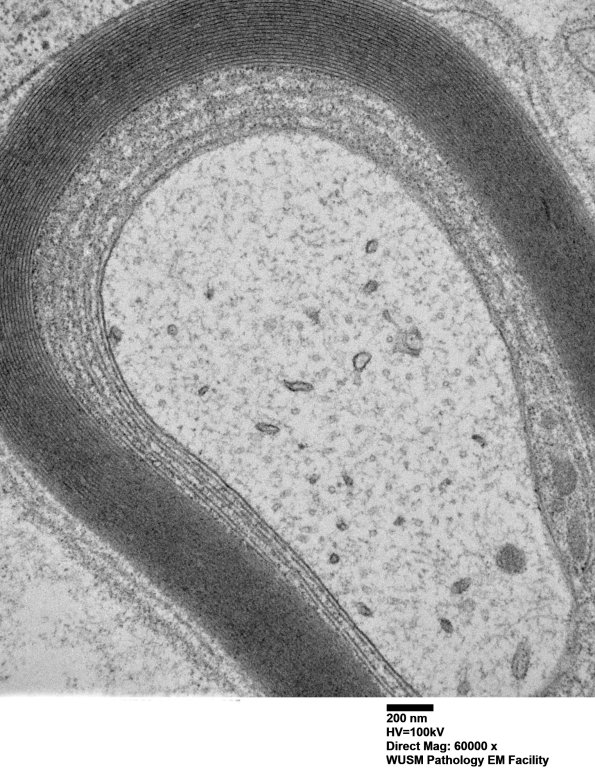

Washington University Experience | PERIPHERAL NEUROPATHY | 13 POEMS SYNDROME | 1B4B (Case 1) Sural_025 - Copy

1B4B (Case 1) Sural_025 - Copy

The same process in a more limited distribution. (electron micrographs)